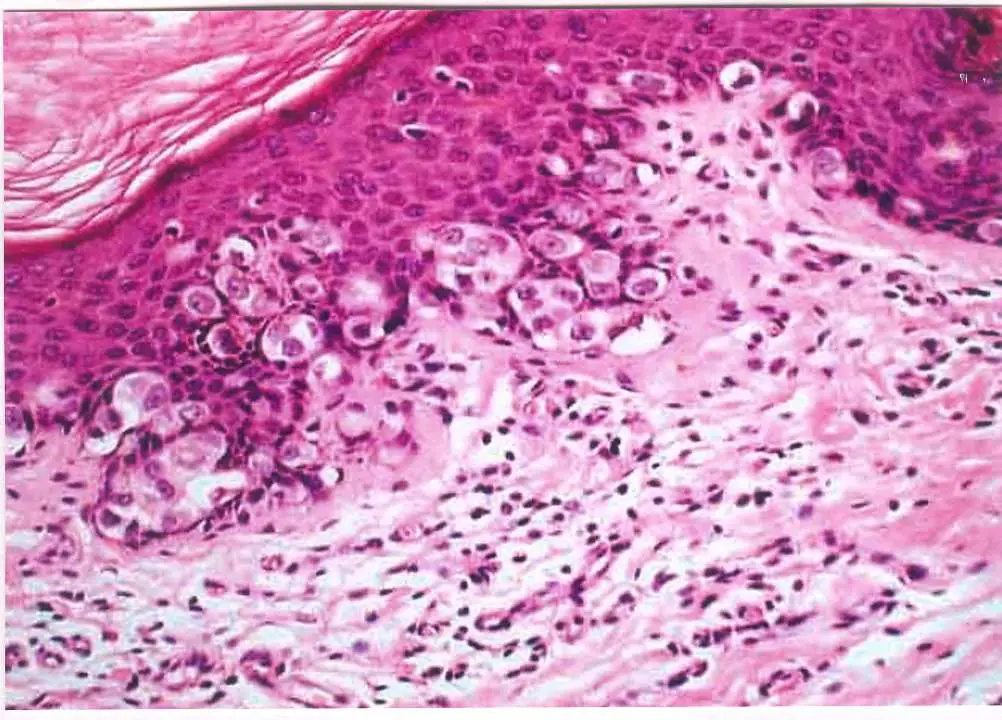

56 歲女性,大陰唇處有一個界限明顯、會癢、表面較紅且會結痂的病變。她接受切片檢查。圖示是病變區在顯微鏡下的 變化。下列有關此病的敘述何者正確?

外陰部佩吉特病(Extramammary Paget disease, EMPD)是一種罕見的上皮內腺癌,好發於大陰唇,臨床表現為界限明顯、紅斑、搔癢、結痂的病變。組織學上以豐富胞質的 Paget 細胞散布於表皮為特徵,且 PAS 染色(periodic acid-Schiff stain)陽性,反映細胞內富含黏多醣(mucopolysaccharides)。

本圖為 H&E 染色之組織切片,可見以下特徵:

Paget 細胞(Paget cells):表皮內散布大量胞質豐富、淡染(pale to clear cytoplasm)的大型上皮細胞,細胞核大、圓形,核仁明顯。這些細胞以巢狀(nests)或散在方式分布於正常鱗狀上皮細胞之間,呈現典型的 pagetoid spread 模式。

表皮結構:Paget 細胞主要分布於表皮下層至中層,部分達表皮全層;表皮角質層可見結痂(crusting),與臨床描述「會結痂」相符。

真皮改變:真皮淺層可見淋巴球及炎症細胞浸潤,無明顯基底膜破壞(符合上皮內病變,非侵犯性)。

整體印象:此組織學形態為外陰部佩吉特病的典型表現——大而淡染的腺上皮細胞散布於鱗狀表皮中,細胞內含大量黏蛋白(mucin),即為 PAS 染色陽性的形態學基礎。